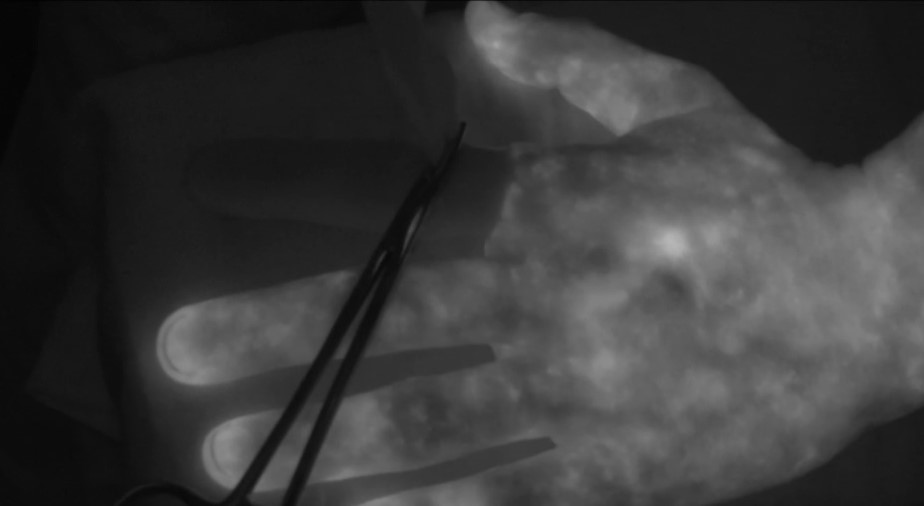

The HSC Foundation is raising $200,000 to purchase a new indocyanine green (ICG) angiography unit.

This state-of-the-art unit helps detect abnormalities in blood flow so that they can be addressed during surgery, thereby avoiding complications later on.

While the Health Sciences Centre Foundation’s Operation Excellence campaign marches toward the finish line, we are conducting a number of related campaigns to enhance patient care and improve patient outcomes. This includes our $200,000 “Fund-A-Need” campaign to purchase a new indocyanine green (ICG) angiography unit. This state-of-the-art unit helps detect abnormalities in blood flow so that they can be addressed during surgery, thereby avoiding complications later on. The unit will be used thousands of times a year, providing patients with better surgical outcomes and easier recoveries.

This indocyanine green (ICG) angiography unit will support a number of surgical specialties across HSC: colorectal, plastics, urology, gynecology, orthopedic, head and neck, and others.